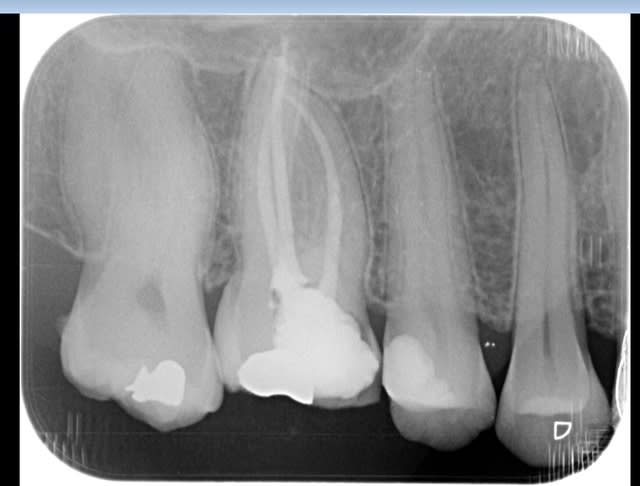

Pas de blouse, pas de radio pour vérifier la longueur.

90 mn 2 molar endo + extrac 38. Un peu lent du à la difficulté à anesthésier (30 mn). les crochets apicaux traités comme si ils n'existaient pas avec le r25.

Maintenant pour peaufiner l'action du sx avant le passage du s1 un petit coup de r25 pour progresser d'avantage n'est pas interdit (pas de fausse route avec pour l'instant)c'est ce que j'ai fait sur ces 2 molaires ou la radio préop laissait présager un peu de sport. )))

connais pas. Mais une de plus 30 mn, résultat reproductible à un train de sénateur, po pom, po pom.) Radio cone en place facultative mais bon des fois je coupe le bout du cone..